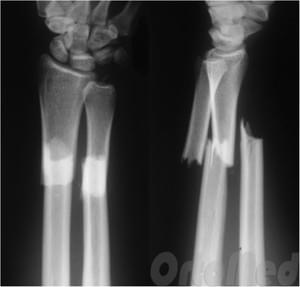

Среди травм нижней части предплечья самым распространенным является перелом лучевой кости в типичном месте. Линия повреждения располагается на несколько сантиметров выше сустава – в самом тонком месте лучевой кости. Именно в этом месте наиболее часто встречаются повреждения, отсюда и название. Выделяют два основных вида травм:

• перелом Смита возникает вследствие падения на согнутую в лучезапястном суставе конечность. Как результат, образуются два отломка: нижний (дистальный) смещается назад и в сторону, верхний – вперед. В некоторых случаях параллельно возникает повреждение шиловидного отростка локтевой кости;

• при переломе Коллеса человек падает на разогнутую в лучезапястном суставе руку. Нижний отломок смещается кпереди и немного латерально (вбок). Движения в суставе ограничены, в месте травмы возникает отек, покраснение, могут прощупываться отломки кости.